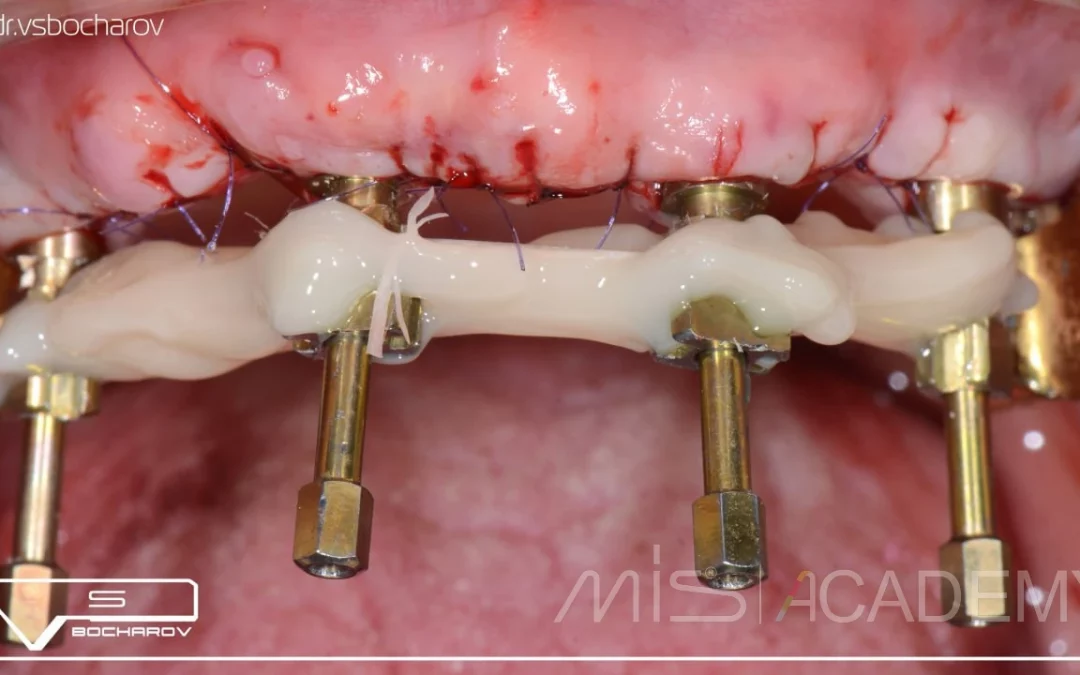

Василий Бочаров | Клинический кейс VB-63

Тотальная реабилитация зубов - Немедленная нагрузка на 4 имплантатах МИС С1, установленных под углом. Ввиду узкого гребня, имплантаты были установлены с небным оголением. - Во фронтальном отделе использованы...